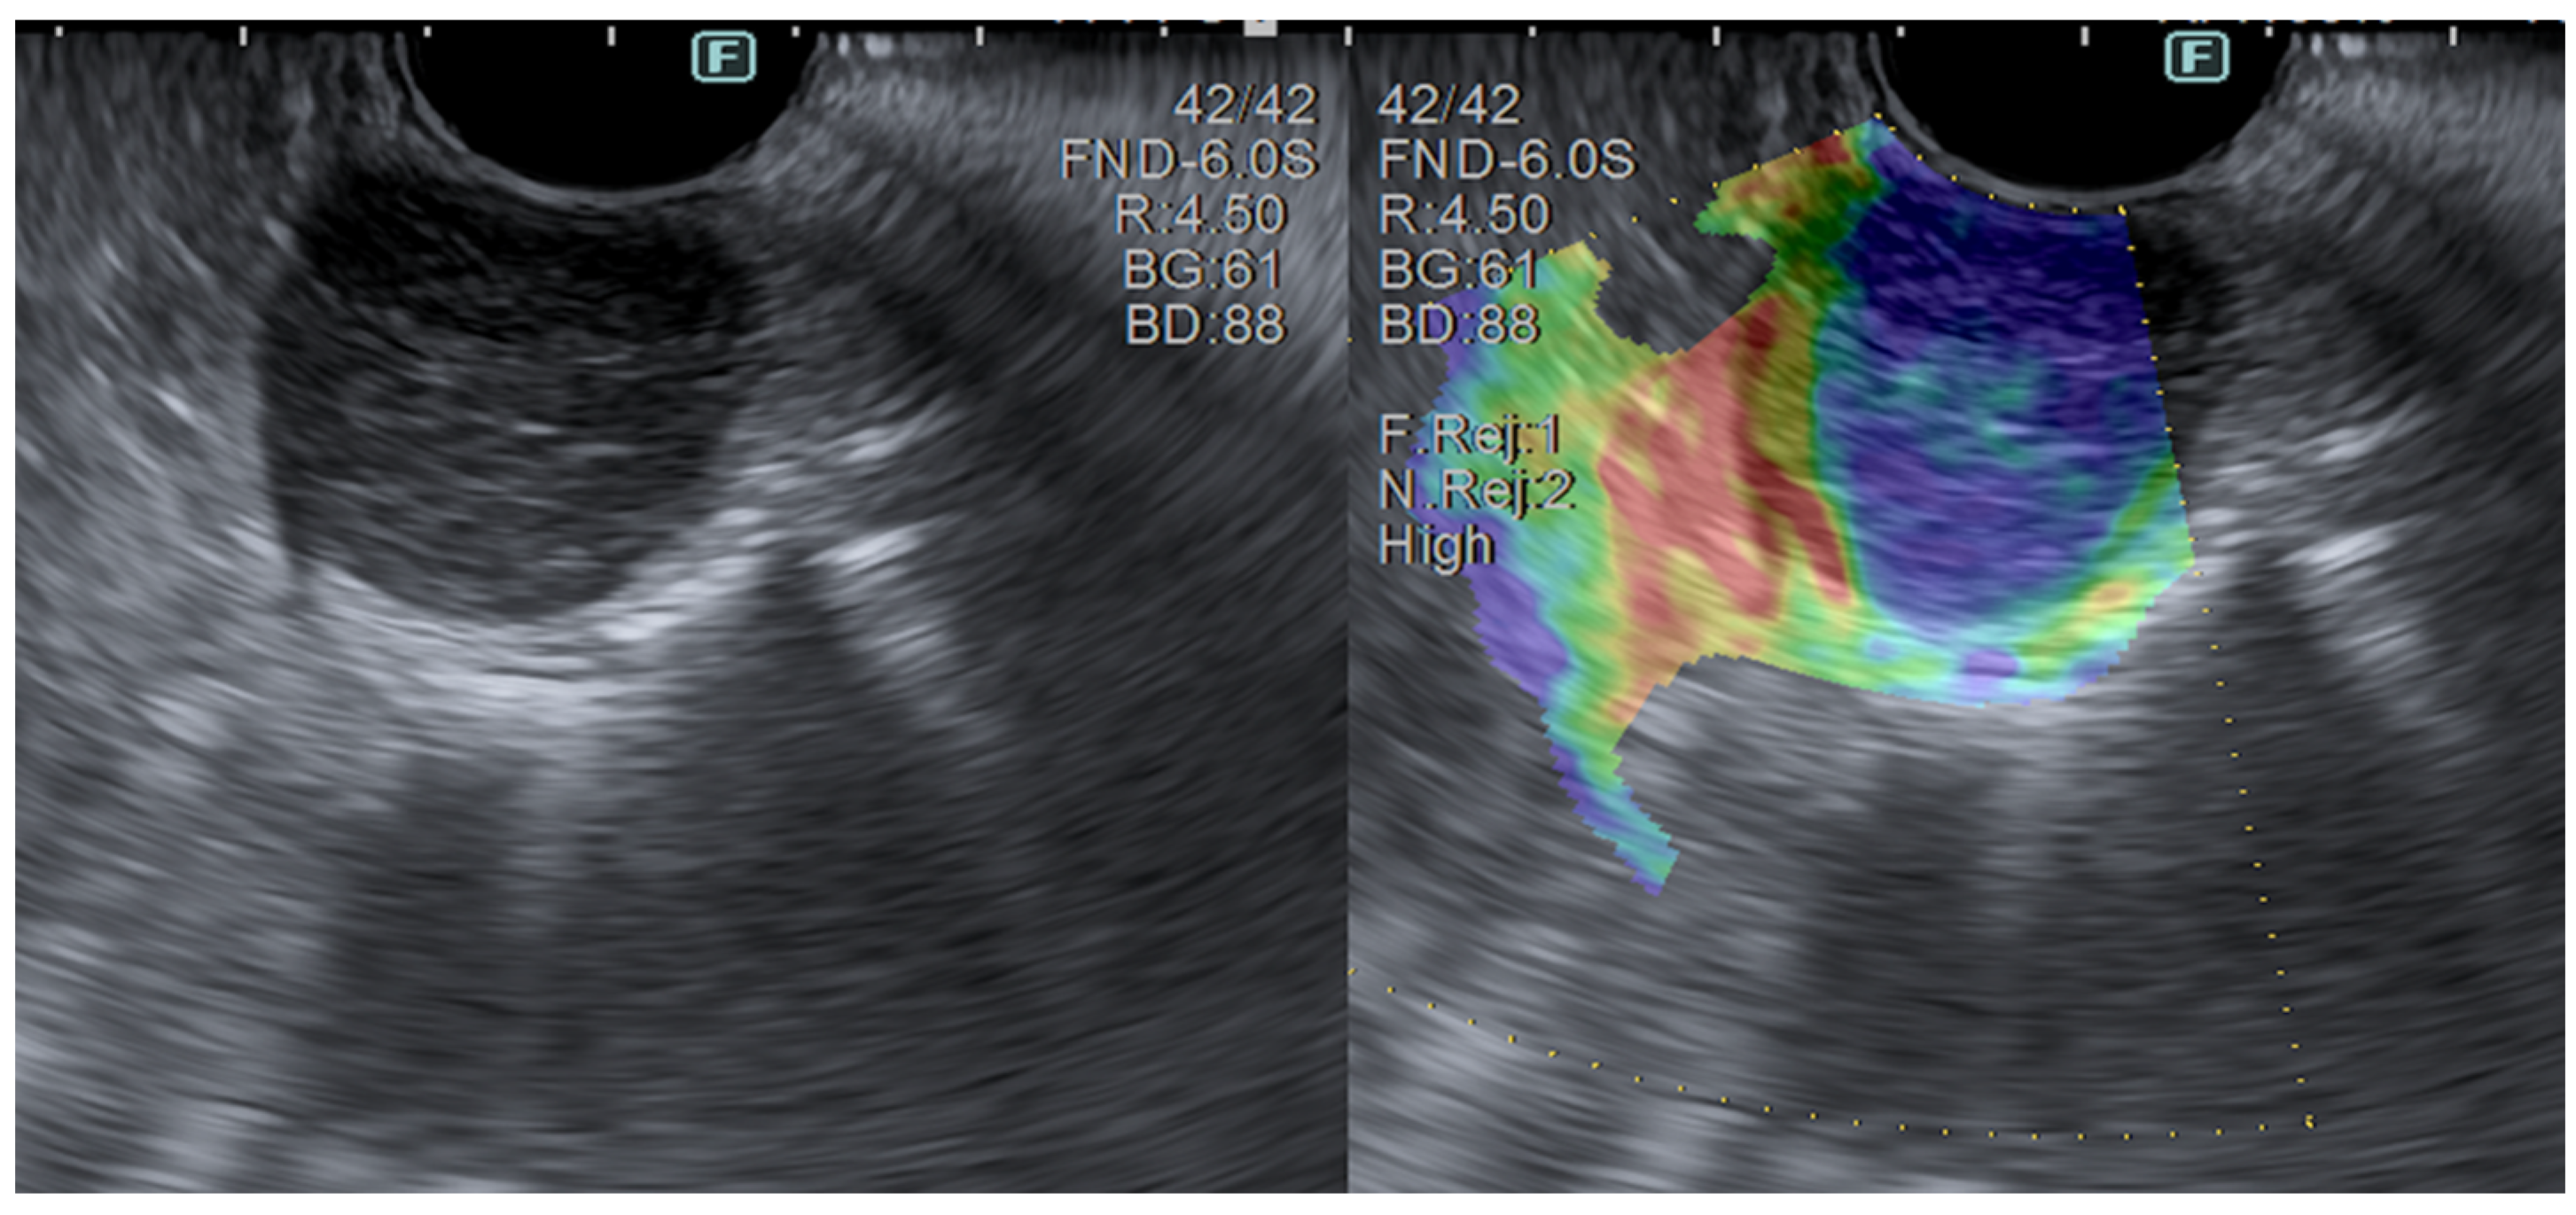

3.1. Color Doppler

3.2. Elastography